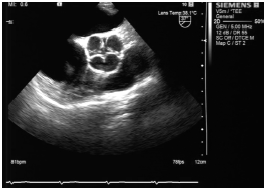

行经食管超声心动图检查:大动脉短轴切面见主动脉窦为四窦,瓣为四瓣,瓣缘增厚,回声增强,呈前后左右排列,左前瓣及右前瓣交界处略粘连,收缩期主动脉瓣开放呈口字形,舒张期关闭呈田字型。开放正常,关闭时可见中央性关闭裂隙,左、右冠状动脉分别起始于左后窦及右前窦(图1,2)。最终诊断为主动脉瓣四叶畸形。

图1 经食管超声心动图示大动脉短轴显示为主动脉瓣关闭状态 医学百科网 | YxBaike.Com